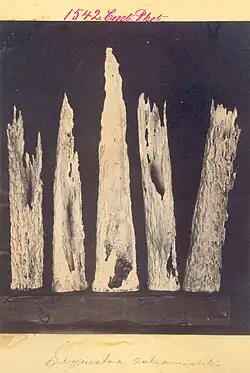

Elle survient en l'absence d'un traitement précoce de l'infection et aboutit à une ostéomyélite chronique. L'interruption de la vascularisation osseuse tant centromédullaire que sous-périostée entraîne une nécrose osseuse avec formation d'un os mort avasculaire, libre dans l'abcès, dénommé séquestre osseux.

- des séquestres osseux (fragment osseux d'aspect dense libre et irrégulier).

Il permet d'étudier surtout l'extension osseuse dans les formes chroniques (aspect hétérogène) et surtout de détecter la présence d'un séquestre, fragment d'os mort qui agit comme un corps étranger et favorise la persistance des fistules : c'est un élément essentiel de l'indication chirurgicale dans les suppurations persistantes. Il permet également d'étudier les localisations vertébrales et sacro-iliaques.

L'inadaptation du traitement peut conduire à l'ostéomyélite chronique avec des lésions cutanées (fistule, ulcération, perte de substance), musculaires (amyotrophie, fibrose rétractile du quadriceps dans les atteintes fémorales), osseuses avec séquestre (perte d'os par séquestrectomie chirurgicale ou élimination spontanée).